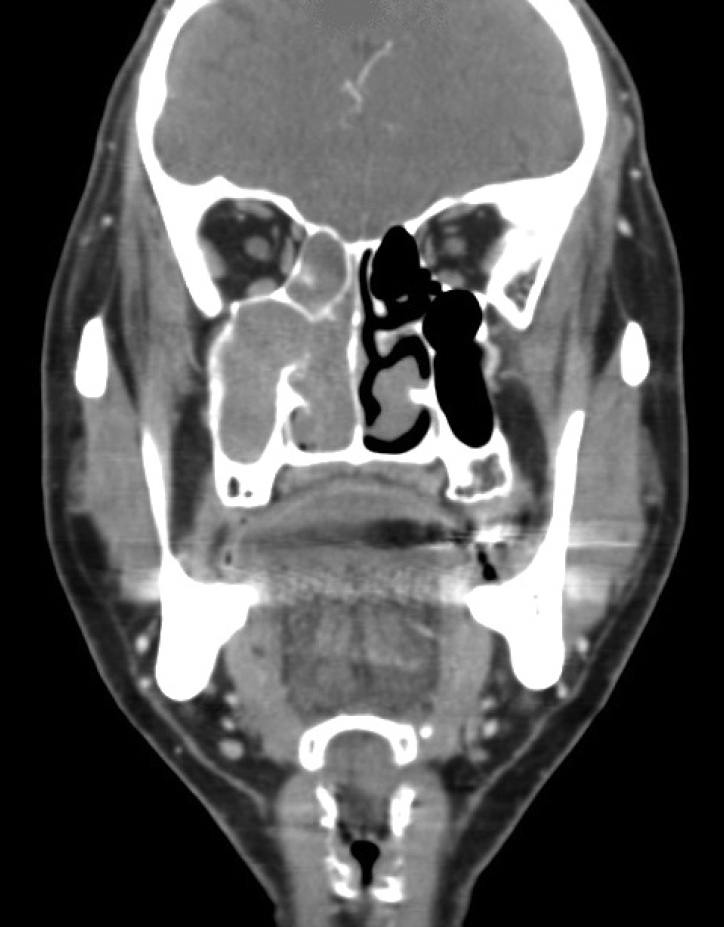

CaseA 59-year-old male presented to the emergency department with profound lethargy, progressive headache, personality changes and mood swings. The symptoms had developed since the last 1 week. The patient had a history of diabetes and depressive disorder, which was diagnosed recently based on the above mentioned symptoms; and he had undergone ESS 6 weeks ago. He had visited our outpatient clinic with a 2-month history of nasal obstruction and epistaxis. He had already been diagnosed as having chronic rhinosinusitis and nasal polyps, but there was no response to medical treatment. In the contrast computed tomography (CT) scan of his paranasal sinuses, there was a soft tissue mass that had completely filled the right maxillary sinus and was extending into the nasal cavity with widening of the maxillary ostium, the ethmoidal infundibulum, and lifting of the ethmomaxillary plate. This mass was diagnosed as inverted papilloma (Fig. 1). He underwent right endoscopic medial maxillectomy under general anesthesia and the diagnosis of inverted papilloma was confirmed by frozen biopsy. Intraoperatively, it was noted that the mass was penetrating into the anterior skull base and there was a 1.5-cm dural defect resulting in CSF leakage following the surgery. The defect was repaired using an underlay technique with the inferior turbinate mucosal flap, and the septal cartilage was sealed with a fibrin sealant Tissucol Duo Quick® (Baxter AG, Vienna, Austria). The lumbar drain was maintained for 3 days postoperatively. He was discharged from the hospital on the seventh day after surgery. During the follow-up period, 3 days before the visiting the emergency room, he complained of non-locaized mild headache and mild lethargy. Also, no obvious CSF leakage was detected on nasal endoscopy (Fig. 2).

NotesAuthor Contribution Conceptualization: Jin Kook Kim. Data curation: Hansol Kim, Taesik Jung. Formal analysis: Hansol Kim, Taesik Jung, Jin Kook Kim. Methodology: Jin Kook Kim. Project administration: Joon Yong Park, Jin Kook Kim. Supervision: Jin Kook Kim. Visualization: Hansol Kim, Taesik Jung. Writing—original draft: Joon Yong Park. Writing—review & editing: Jin Kook Kim. Fig. 1.In the CT scan of paranasal sinuses, the right maxillary sinus was filled with a heterogeneous soft tissue mass. The mass was extending into the nasal cavity with widening of the maxillary ostium. Fig. 2.Endoscopic finding of the dural repair site. There was no cerebrospinal fluid leakage at postoperative 6 weeks. REFERENCES1. DelGaudio JM, Ingley AP. Treatment of pneumocephalus after endoscopic sinus and microscopic skull base surgery. Am J Otolaryngol 2010;31(4):226-30.